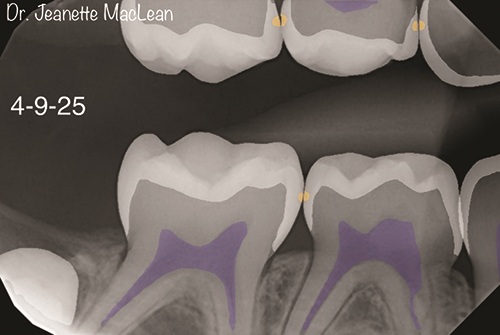

Figs. 2a and 2b: Overjet identifies incipient caries lesions, highlighted in yellow. Surgical intervention is not indicated at this time. Nonsurgical treatment with silver diamine fluoride is offered and accepted by parent.

Figs. 3a and 3b: Five-month follow-up BWs (DEXIS Titanium imaging).

Figs. 4a and 4b: Overjet confirms the incipient lesions are stable after treatment with silver diamine fluoride (Advantage Arrest, Elevate Oral Care). The lesions between the mandibular right primary molars are no longer detectable.